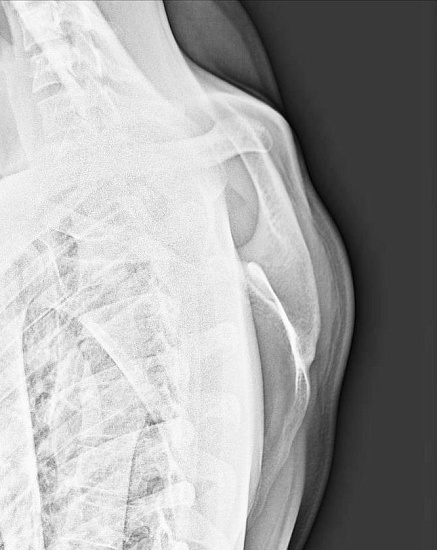

Рентгенография лопатки – важный метод прицельного исследования, который позволяет оценить состояние лопатки.

Диагностическая услуга выполняется в двух проекциях.

Рентген позволяет оценить наличие костно-травматической патологии лопатки.